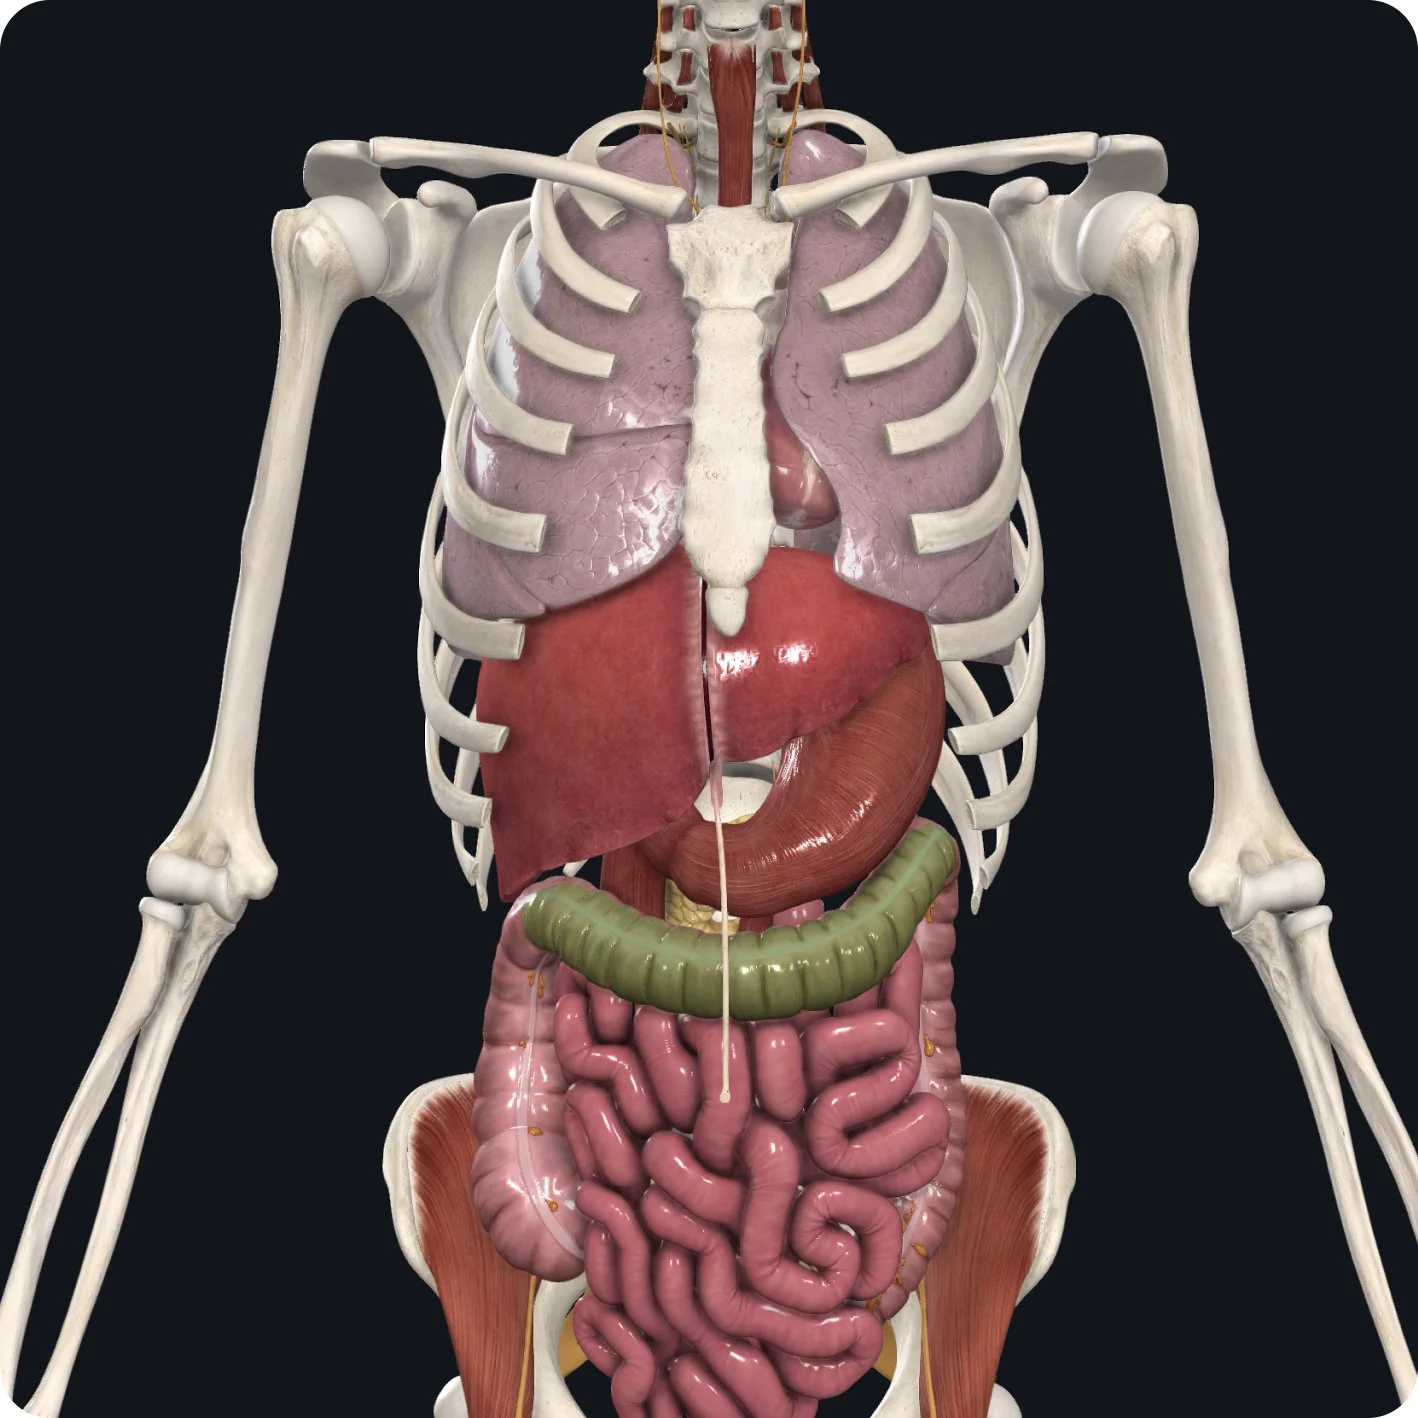

In addition to some motor and sensory functions, the vagus nerve also supports parasympathetic functions— the rest and digest functions— slowing down our heart rate, lowering the rate of respiration, and increasing the rate of digestion, all within the same nerve, making it a very complex nerve.

Sensory: General sense to the inferior pharynx and larynx, as well as the thoracic and abdominal organs

Parasympathetic: Thoracic and abdominal viscera up to 2/3 of the transverse colon (supporting digestion, heart rate, blood pressure, and immune system responses)

• Visualize the pathway, from the medulla, moving alongside cranial nerves IX and XI to exit through the jugular foramen, moving down the cervical spine alongside the carotid artery and internal jugular vein to reach target areas, and extending down into additional targets in the thoracic and abdominal cavities.

The vagus nerve has both sensory and parasympathetic function within the organs of the thoracic and abdominal cavities, up until 2/3 of our transverse colon.